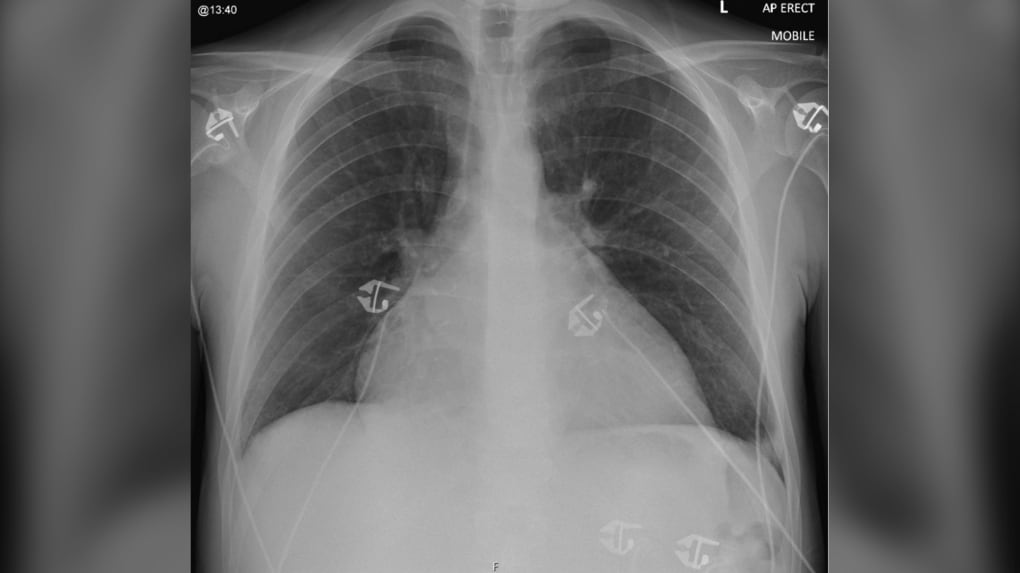

21-year-old experiences heart failure after drinking four energy drinks a day for two years: case study